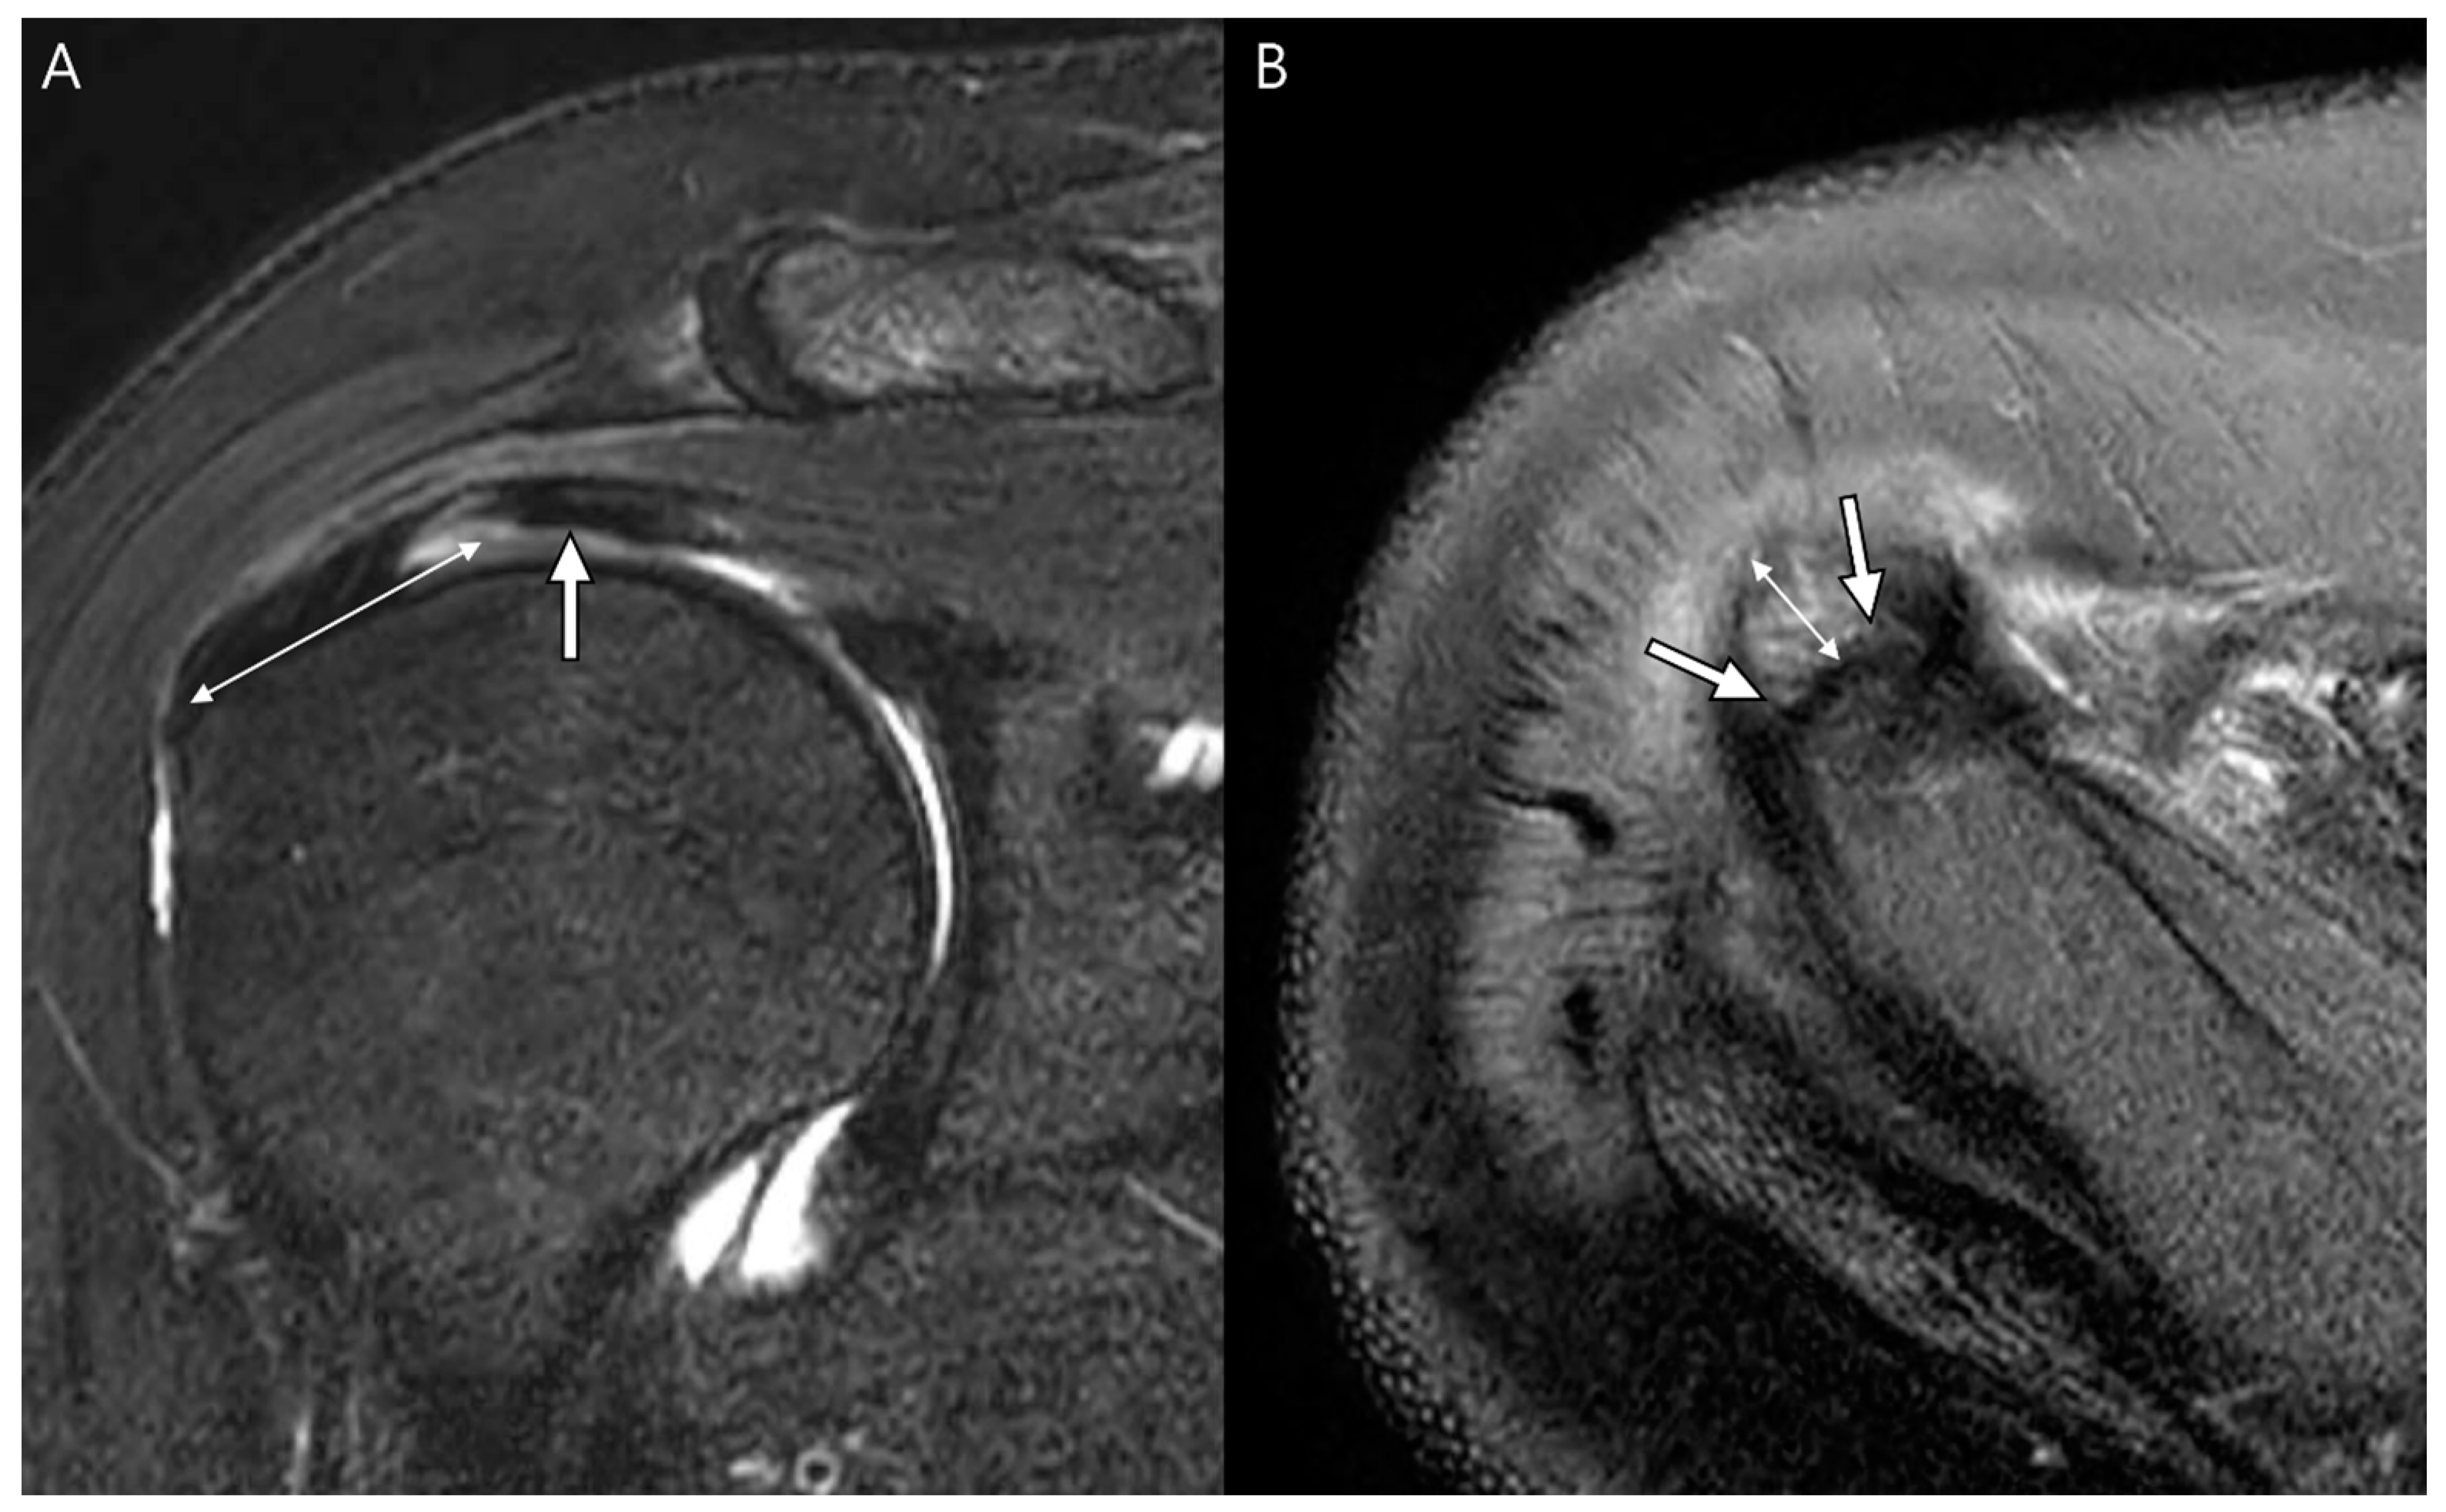

Imaging features of supraspinatus rotator cuff tear. resonance... Download Scientific

Imaging features of supraspinatus rotator cuff tear. resonance... Download Scientific Rotator Cuff Tear Supraspinatus Advances in surgical techniques for rotator cuff repair include less invasive procedures. A supraspinatus tear often occurs from falling onto an outstretched arm, or from throwing activities. What are the symptoms of a rotator cuff tear? these four muscles (supraspinatus, infraspinatus, subscapularis, and teres minor) stabilize the. In many cases, torn tendons begin by fraying. It is one of. Rotator Cuff Tear Supraspinatus.

Imaging features of supraspinatus rotator cuff tear. resonance... Download Scientific Rotator Cuff Tear Supraspinatus A supraspinatus tear often occurs from falling onto an outstretched arm, or from throwing activities. It is one of the four rotator cuff muscles. Rotator cuff tear symptoms include: In many cases, torn tendons begin by fraying. these four muscles (supraspinatus, infraspinatus, subscapularis, and teres minor) stabilize the. the supraspinatus muscle runs along the top of the scapula. Rotator Cuff Tear Supraspinatus.